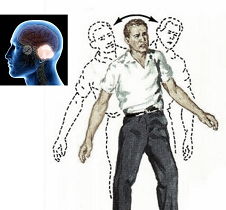

Ataxia refers to a loss of coordination and balance, that causes difficulty in speech and swallowing, unsteady walking, hand clumsiness, and affected eye movements. Ataxia is actual loss of balance and coordination and should be differentiated from dizziness. The walking is unsteady or with the feet set wide apart to maintain better balance, difficulty with